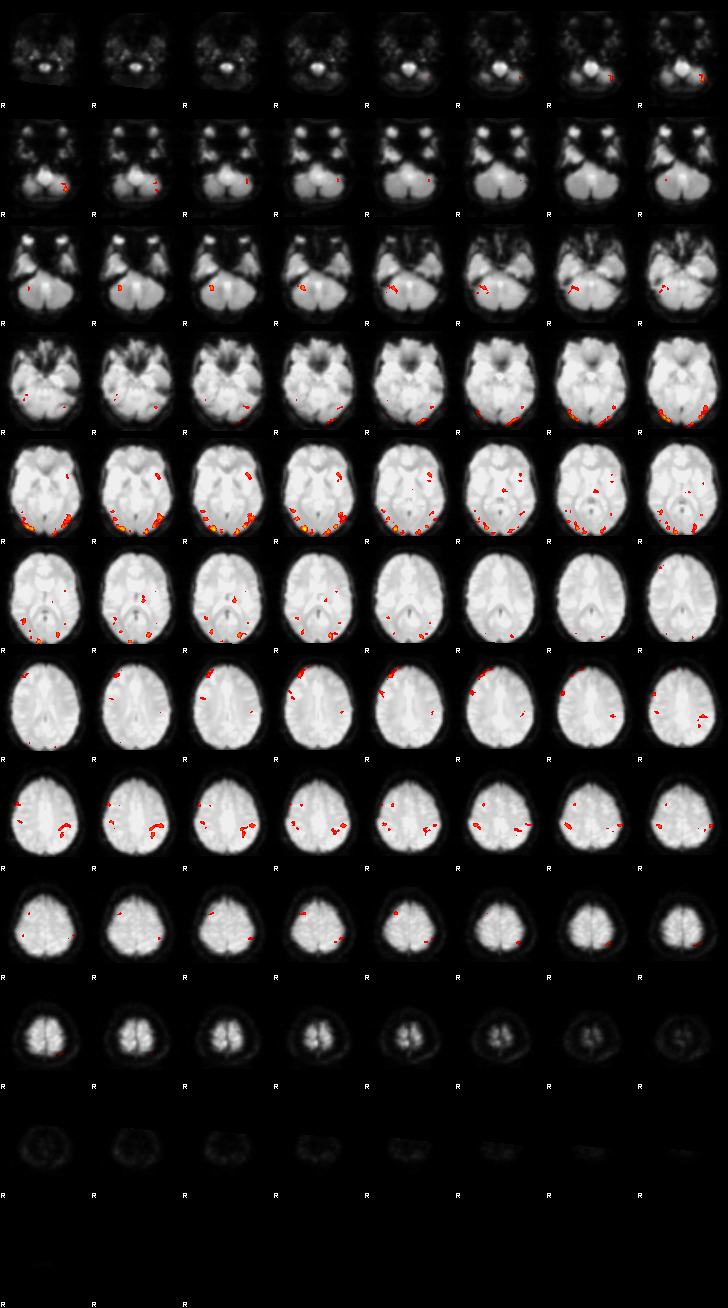

Visualization of First-level Design and Results (Run 1)#

Below, the design matrix and selected results from the first run are shown. Since both runs use the same design and contrasts, the results of the second run can be explored using the same approach.

Let’s now display the thresholded activation maps. A voxelwise threshold of Z > 3.1 was applied, followed by cluster-level correction at p < 0.05 (corrected for multiple comparisons).

zstat1 - C1 (incongruent)

display(Markdown("#### Incongruent"), rendered_thresh_zstats1)

Incongruent